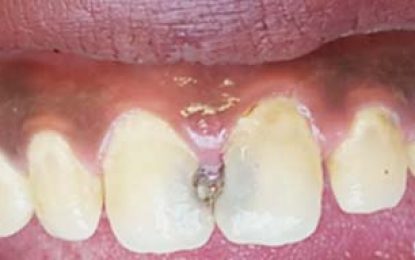

Dear Editor, When one looks at the spontaneous and passionate response by civil society to the parking imbroglio it shows clearly that all of Guyana wants to see transparency, accountability and more...Feb 26, 2017 KNews News Comments Off on DENTAL HEALTH…FILLINGS: DO YOU NEED THEM?

By Dr. Neromini Fagu Over the last few weeks we have spoken about fillings and some of the options available. This week I would like to discuss indications for a filling and the factors that will...Feb 26, 2017 KNews Cartoons, Features / Columnists Comments Off on Sunday Cartoon